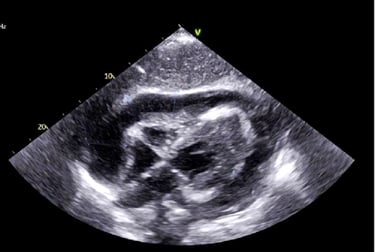

We start immediately at the bedside with probe in hand, introducing core FAST/RUSH protocols so you begin scanning on the very first minute of class. Hands-on practice is intense and structured: learners develop the hand-eye skills to acquire clear views quickly while faculty reinforce system controls, Doppler use, and targeted protocols that directly impact clinical decisions.

Scanning sessions are interwoven with short, high-yield discussions that tie anatomy and findings back to real patient scenarios. You repeatedly cycle through focused clinical targets — trauma windows, fluid detection, basic vascular access guidance — so that pattern recognition becomes automatic.

Hands-On POCUS- Point of Care Ultrasound